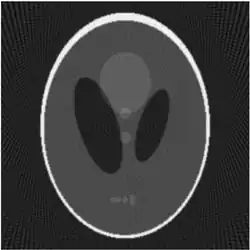

Radon transform of the indicator function of two squares shown in the image below. Lighter regions indicate larger function values. Black indicates zero.

Original function is equal to one on the white region and zero on the dark region.